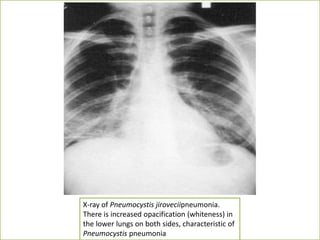

• CXR:

– Can be normal or diffuse bilateral

infiltrates extending from the perihilar

region are visible in most patients with P

carinii pneumonia (PCP).

X-ray of Pneumocystis jiroveciipneumonia.

There is increased opacification (whiteness) in

the lower lungs on both sides, characteristic of

Pneumocystis pneumonia